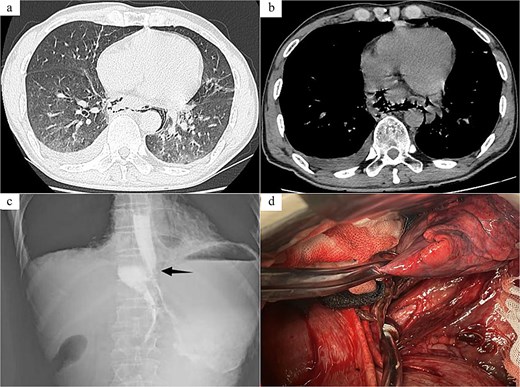

Case 1: The patient, a 67-year-old male, was admitted to Emergency Department due to “hematemesis for 2 h, abdominal and thoracic pain for 1 h.” On admission, imaging studies including chest and abdomen computed tomography (CT) revealed esophageal distal middle-third wall thickening, perihilar pleural edema, pericardial effusion (Fig. 1a and b). Esophagus echoendoscopy showed contrast agent leakage into the perihilar region (Fig. 1c). Electrocardiogram showed no abnormalities. Blood routine test showed that white cell count 11.7 × 109/L, neutrophil count 10.4 × 109/L, neutrophil percentage 89%. In summary, the diagnosis was SRE. In emergent surgery under general anesthesia, laparoscopic repair of esophageal tear was performed. Intraoperative exploration revealed a rupture site located in the lower segment of the esophagus, with a length of about 4.0 cm (Fig. 1d), esophagus and gastric contents (stomach) overflowed at the site of the injury. The surgical steps included removal of foreign bodies, copious irrigation with normal saline until clear, and iodine solution irrigation for disinfection. Subsequently, the surgery trimmed the severely contaminated mucosa and muscular layer of the esophageal perforation until slight oozing of blood, involved interrupted absorbable sutures for full-layer closure of the esophageal perforation, reflushed with iodine solution. Drainage tubes were placed in the mediastinum and chest cavity, respectively. And a gastric tube and a duodenal feeding tube were indwelled. Postoperative care included anti-infection, protective measures, and parenteral nutrition. On the second day after surgery, the patient developed febrile maintained at 38.1°C–38.6°C, and a repeat blood routine examination showed low white blood cell count. The heart rate remained around 125 beats per minute, the blood pressure fluctuated between 80–90/50–60 mmHg, with palpitations, apathy, and involuntary spasms in the limbs. Infectious shock was considered after multi-disciplinary discussion, and the patient was transferred to the intensive care unit (ICU) for upgraded antibiotics (imipenem, vancomycin) therapy, and was given ventilator-assisted breathing, fluid infusion, blood transfusion, enteral nutrition, and other supportive treatment. After 7 days of treatment in the ICU, the septic shock was corrected and the patient was transferred back to the general ward for treatment. Subsequently, the patient was reexamined with upper gastrointestinal radiography and chest CT, which suggested that there was no leakage or stenosis at anastomosis of the esophagus. After a total of 18 days of fasting, the patient began to resume a diet and was discharged in good health.

Radiology images and emergency surgery photos of spontaneous esophageal rupture (Case 1). (a and b) Chest and abdomen computed tomography revealed mediastinal emphysema around the lower segment of the esophagus. (c) Esophagus echoendoscopy showed contrast agent leakage into the perihilar region (arrow). (d) Emergency surgery revealed a rupture site located in the lower segment of the esophagus, with a length of about 4.0 cm, and involved interrupted absorbable sutures for full-layer closure of the esophageal perforation.